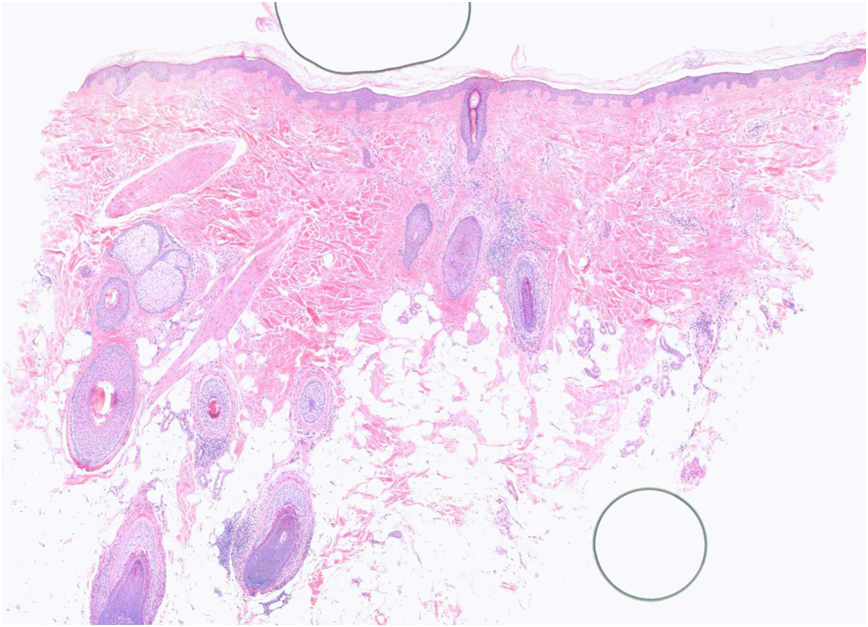

60 Year old female with frontal scalp - Incisional Biopsy for vertical sectioning Few months history of hair loss Bald patches with short hairs frontal and temporal hairline with areas of scanty